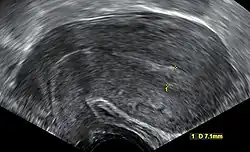

![]() | |

| An ultrasound showing a gestational sac containing a yolk sac but no embryo | |